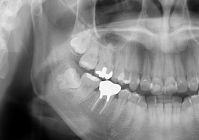

今回は、日本歯周病学会の専門医検索から当院を受診された20代女性のケースをご紹介します。

(掲載にあたり、画像については患者さまご本人の承諾をいただいております。)

3か月ほど前、銀歯のふちに穴があいているとのことで近隣の歯科医院を受診されたそうです。

痛みはなかったものの、虫歯が神経の近くまで進行しているとの説明を受け、根管治療(歯の神経の治療)が始まりました。

週2回の通院で1か月以上治療を続け、銀歯を被せて治療が終了した直後から、

噛んだときの鈍い痛みが現れ、のちに歯ぐきの腫れも出てきたとのことです。

かかりつけの先生からは、

「歯が割れて歯周病を起こしている可能性があります。抜歯してブリッジにしましょう。」

と説明され、患者さんは大きな不安を抱えたまま「専門医」を検索し、当院を受診されました。

■ 精密検査で見えてきた"本当の原因"

当院で、歯周病検査・咬合検査・動揺度検査などを行ったところ、

炎症や症状を引き起こしていた直接的な原因が確認できました。

必要な処置を行ったところ、腫れや不快感は徐々に落ち着き、

結果として抜歯を回避できたケースとなりました。